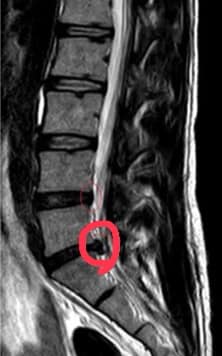

Cervical Spine Treatment Cases 腰椎治療案例 #今天來聊巨大骨刺為何可以吸收回去! #椎間盤突出需要多久才能吸收呢? #馬尾神經症候... 2020.09.08 #典型假性坐骨神經痛 #原來是梨狀肌症候群 #核磁共振排除椎間盤突出 #抽絲剝繭真相大... 2020.08.13 #嚴重椎管狹窄醫案 #感謝台北林大哥熱情見證 #從寸步難行到輕快漫步 #鍛鍊多裂肌的重... 2020.08.12 #椎間盤突出可以吸收回去嗎 #微針治療原理是什麼 #何時一定要接受神外開刀 #一張圖秒... 2020.08.11 #感謝花蓮鄉親林大姐熱情見證 #一分鐘認識椎管狹窄 #原本痛到無法走路打算開刀了 #脊... 2020.08.01 #感謝新莊區林先生熱情見證 #椎間盤突出跟纖維環裂隙的關係 #纖維環破裂突出可以不... 2020.07.28 #逆轉勝又一發case #原本疼痛一年多想說一定要手術治療了 #八週治療後症狀全部消失 #... 2020.07.25 #巨大椎間盤突出一定要開刀嗎 #除了開刀以外的選擇 #感謝台北市吳先生熱情見證 2020.07.24 #腰椎滑脫的疼痛心酸誰人知啊 #一分鐘瞭解腰椎滑脫 #哪一種情況需要積極開刀 #要如何... 2020.07.21 #巨大椎間盤脫垂一定要開刀嗎? #感謝新店林先生熱情見證受訪 #西醫手術有那些選擇... 2020.07.02 #纖維環裂隙AnnularFssures #MRI看起來不嚴重卻嚴重困擾患者 #感謝桃園市蕭先生熱情見... 2020.06.19 #骨刺有可能吸收回去嗎?? #疼痛超過六年的特殊案例探討 #MRI核磁共振前後對比 #感謝... 2020.06.14 #坐骨神經痛一定要開刀嗎 #突出的骨刺真的可以自己吸收嗎 #最新英國醫學期刊BMJ的看... 2020.05.30 #骨刺跟突出髓核有可能吸收回去嗎?? #特殊案例探討 #核磁共振一年後對比 2020.05.29 #從醫以來第一次碰到薦椎Tarlov cyst囊腫#左邊紅色圈圈是個案,右邊是國外案例#腰... 2020.05.23 ← 上一頁 10 11 12 13 14 下一頁 →